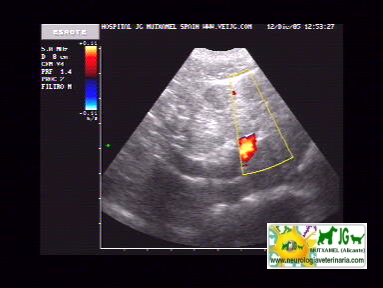

intentamos buscar el shunt portosistémico, pero no es visible ni con el doppler |

video de ecografía con doppler: |